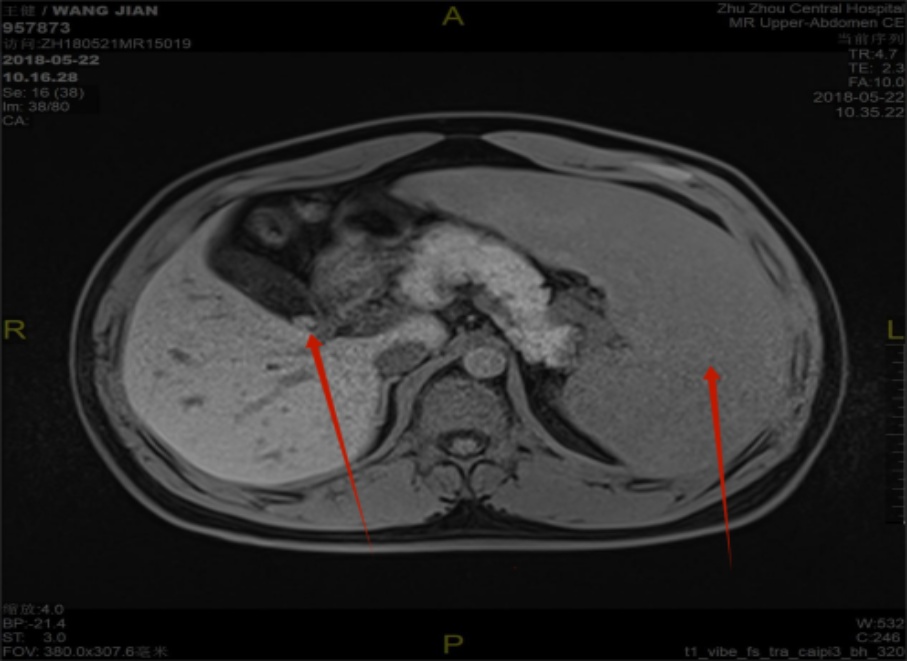

本研究共纳入9例HS患者,其中外科治疗7例,内科治疗2例。患者均为本中心连续收治病例。年龄中位数为30岁(8~64岁),其中成年人5例、青少年4例;男性6例、女性3例。共有4例患者具有明确家族遗传史。所有患者入院时均表现为皮肤巩膜黄染、脾肿大及不同程度的贫血。其中轻度贫血2例,中度贫血5例,重度贫血2例;2例患者合并腹痛症状(详见表1)。全部患者均接受骨髓穿刺活检,结果显示骨髓增生活跃,红系显著增生(图1),提示溶血性贫血特征。共4例患者完成基因检测,突变基因包括SLC4A1、ANK1、SPTB,其中以SPTB突变最为常见(2例) (图2)。影像学检查显示所有患者均存在不同程度的脾肿大(图3)。合并症方面:外科治疗组中6例患者伴胆囊结石,其中5例为单纯胆囊结石,另1例合并胆总管结石。1例合并乙肝肝硬化;内科治疗组中1例患者伴EB病毒感染。患者总体住院时间中位数为13天(8~35天)。外科组住院时间中位数13天(8~35天),内科组住院时间中位数12天(10~14天)。外科患者术后病理结果显示脾脏显著淤血、红髓减少并萎缩(图4),胆囊标本中5例存在慢性胆囊炎伴胆囊结石(图5)。

Figure 3. MRI showing gallstones and splenomegaly in the patient (indicated by the arrow)

3. 患者MRI可见胆囊结石、脾大(箭头所指)